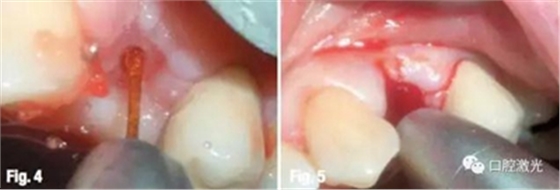

通過(guò)測(cè)量,種植的安全深度為12mm。選擇波長(zhǎng)為2780nm水激光(Er,Cr:YSGG),在浸潤(rùn)局部麻醉后,利用Z4/14激光工作尖在24中心處進(jìn)行切割氣化。激光設(shè)置為功率3W、脈沖能量150mJ、50%水、50%氣。激光發(fā)射方向由臨近牙齒和骨的形態(tài)決定。

當(dāng)?shù)竭_(dá)適合深度后,再沿水平方向適當(dāng)延伸。先手動(dòng)安裝種植體,在利用扭力扳手設(shè)定為廠家推薦最大扭矩進(jìn)行安裝,直到將種植體安裝牢固。